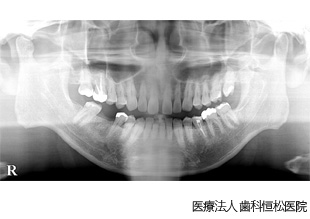

【症例1】上顎All-on-4(6)、下顎両側臼歯インプラント治療

- 治療前

- 治療後

- 治療名

- 上顎All-on-4(6)、下顎両側臼歯インプラント治療

- 費用

- 5,670,830円(税込)

- 費用内訳

- 上顎:3,509,000円(税込)、下顎:2,161,830円(税込)

- 期間

- 1年2ヵ月

治療内容

患者様の症状

重度の歯周病が進行し、上顎は全顎、下顎は両側臼歯が抜歯となった患者様。欠損部に対してインプラント治療を希望。

治療法

最終的な歯の形や位置を想定してシミュレーションを行い、各部位に対応した専用のガイド(サージカルステント)を作製。ガイドを使用してインプラントを適切な位置に植立。植立後、約3ヵ月で各部位に仮歯を装着し、清掃性、審美性、噛み合わせのバランスを確認。その後、問題がないことを確認して最終的な人工歯を装着。なお、治療は下顎両側部から開始し、上顎についても下顎と並行して治療を進行した。

治療結果

機能性・審美性ともに良好に回復。

※治療結果は患者様によって個人差があります。